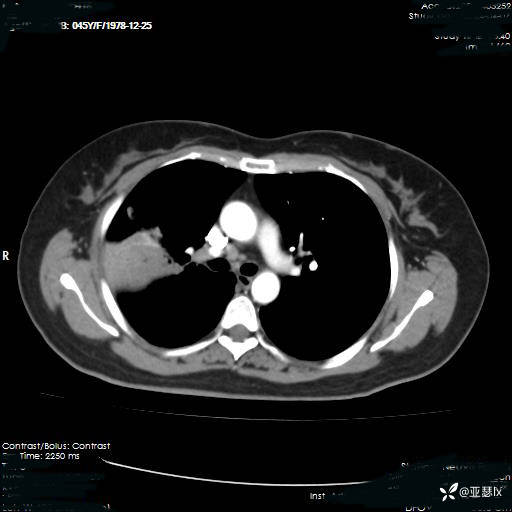

患者体温有所改善,但影像学未见明显变化,后续行肺穿刺活检检查。

总结与讨论

肺实变究竟为何病因:非典型病原体?机化性肺炎?还是其他非感染性因素? @丁香园病例库